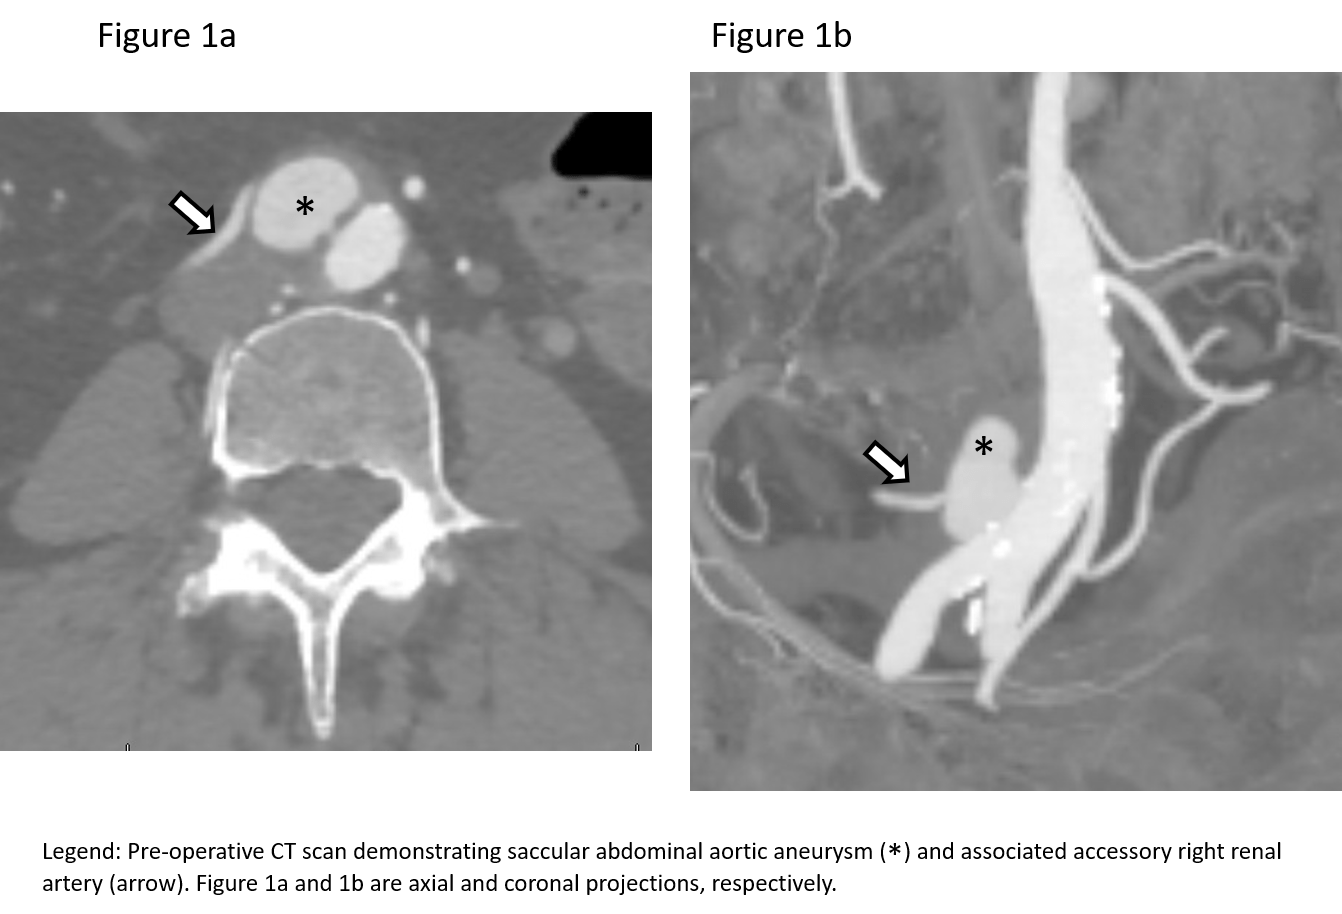

A 68-year-old female with a history of hypertension and hyperlipidemia had been recently diagnosed with breast cancer. Of interest, she had no history of any rheumatologic disorders, nor any active infection. She underwent mastectomy and was in complete remission. She was subsequently being evaluated for breast reconstruction by Plastic Surgery. This required a CT scan of the abdomen and pelvis, which disclosed the presence of an abdominal aortic pseudoaneurysm closely associated with an accessory renal artery (Figures 1a and 1b). The portion that emanated from the accessory right renal artery measured approximately 2.1 x 2.6 cm.

Due to its location and geometry, it also gave the appearance of being a localized aortic dissection. She was completely asymptomatic and denied any history of abdominal or flank pain. She denied arterial surgery. Review of a CT scan obtained 10 years ago did not demonstrate any abdominal arterial abnormalities. Her physical exam was completely benign with normal femoral and lower extremity arterial pulses.